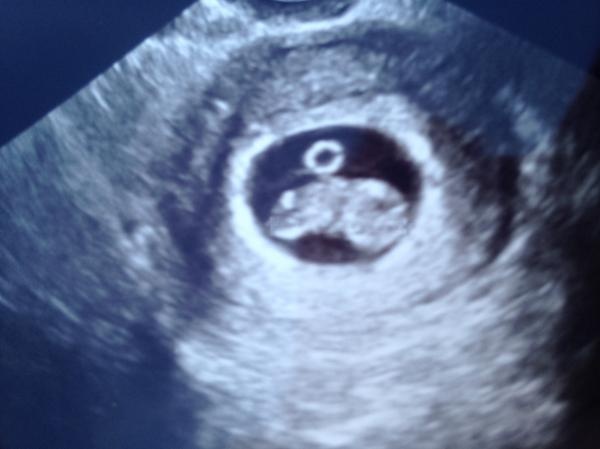

BF Januari 2015

Bildtråd: